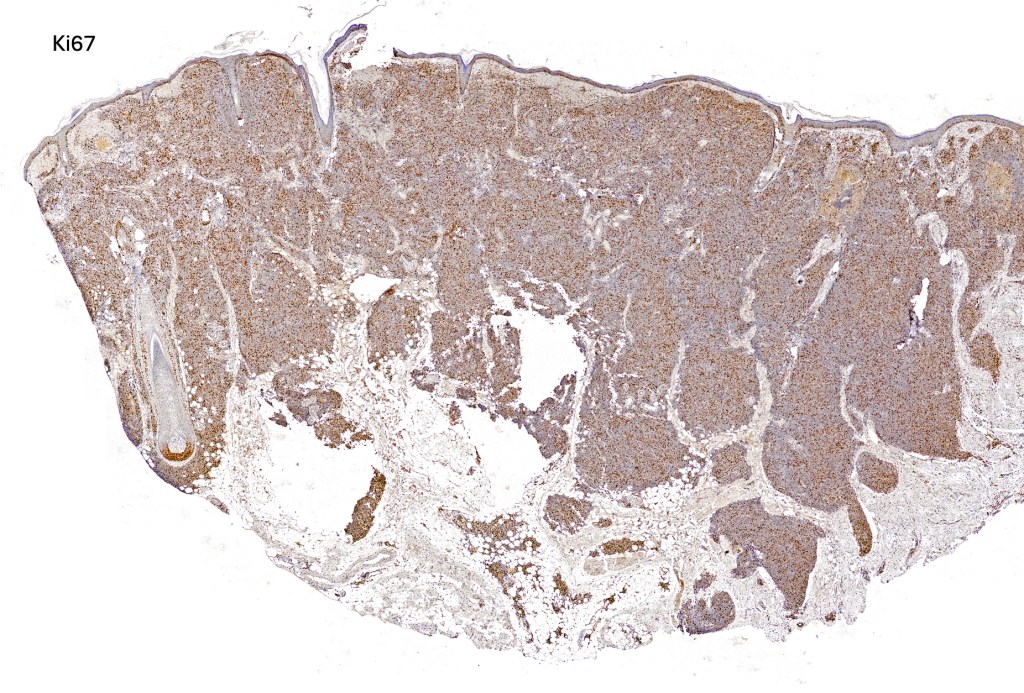

. Marked ki67 expression